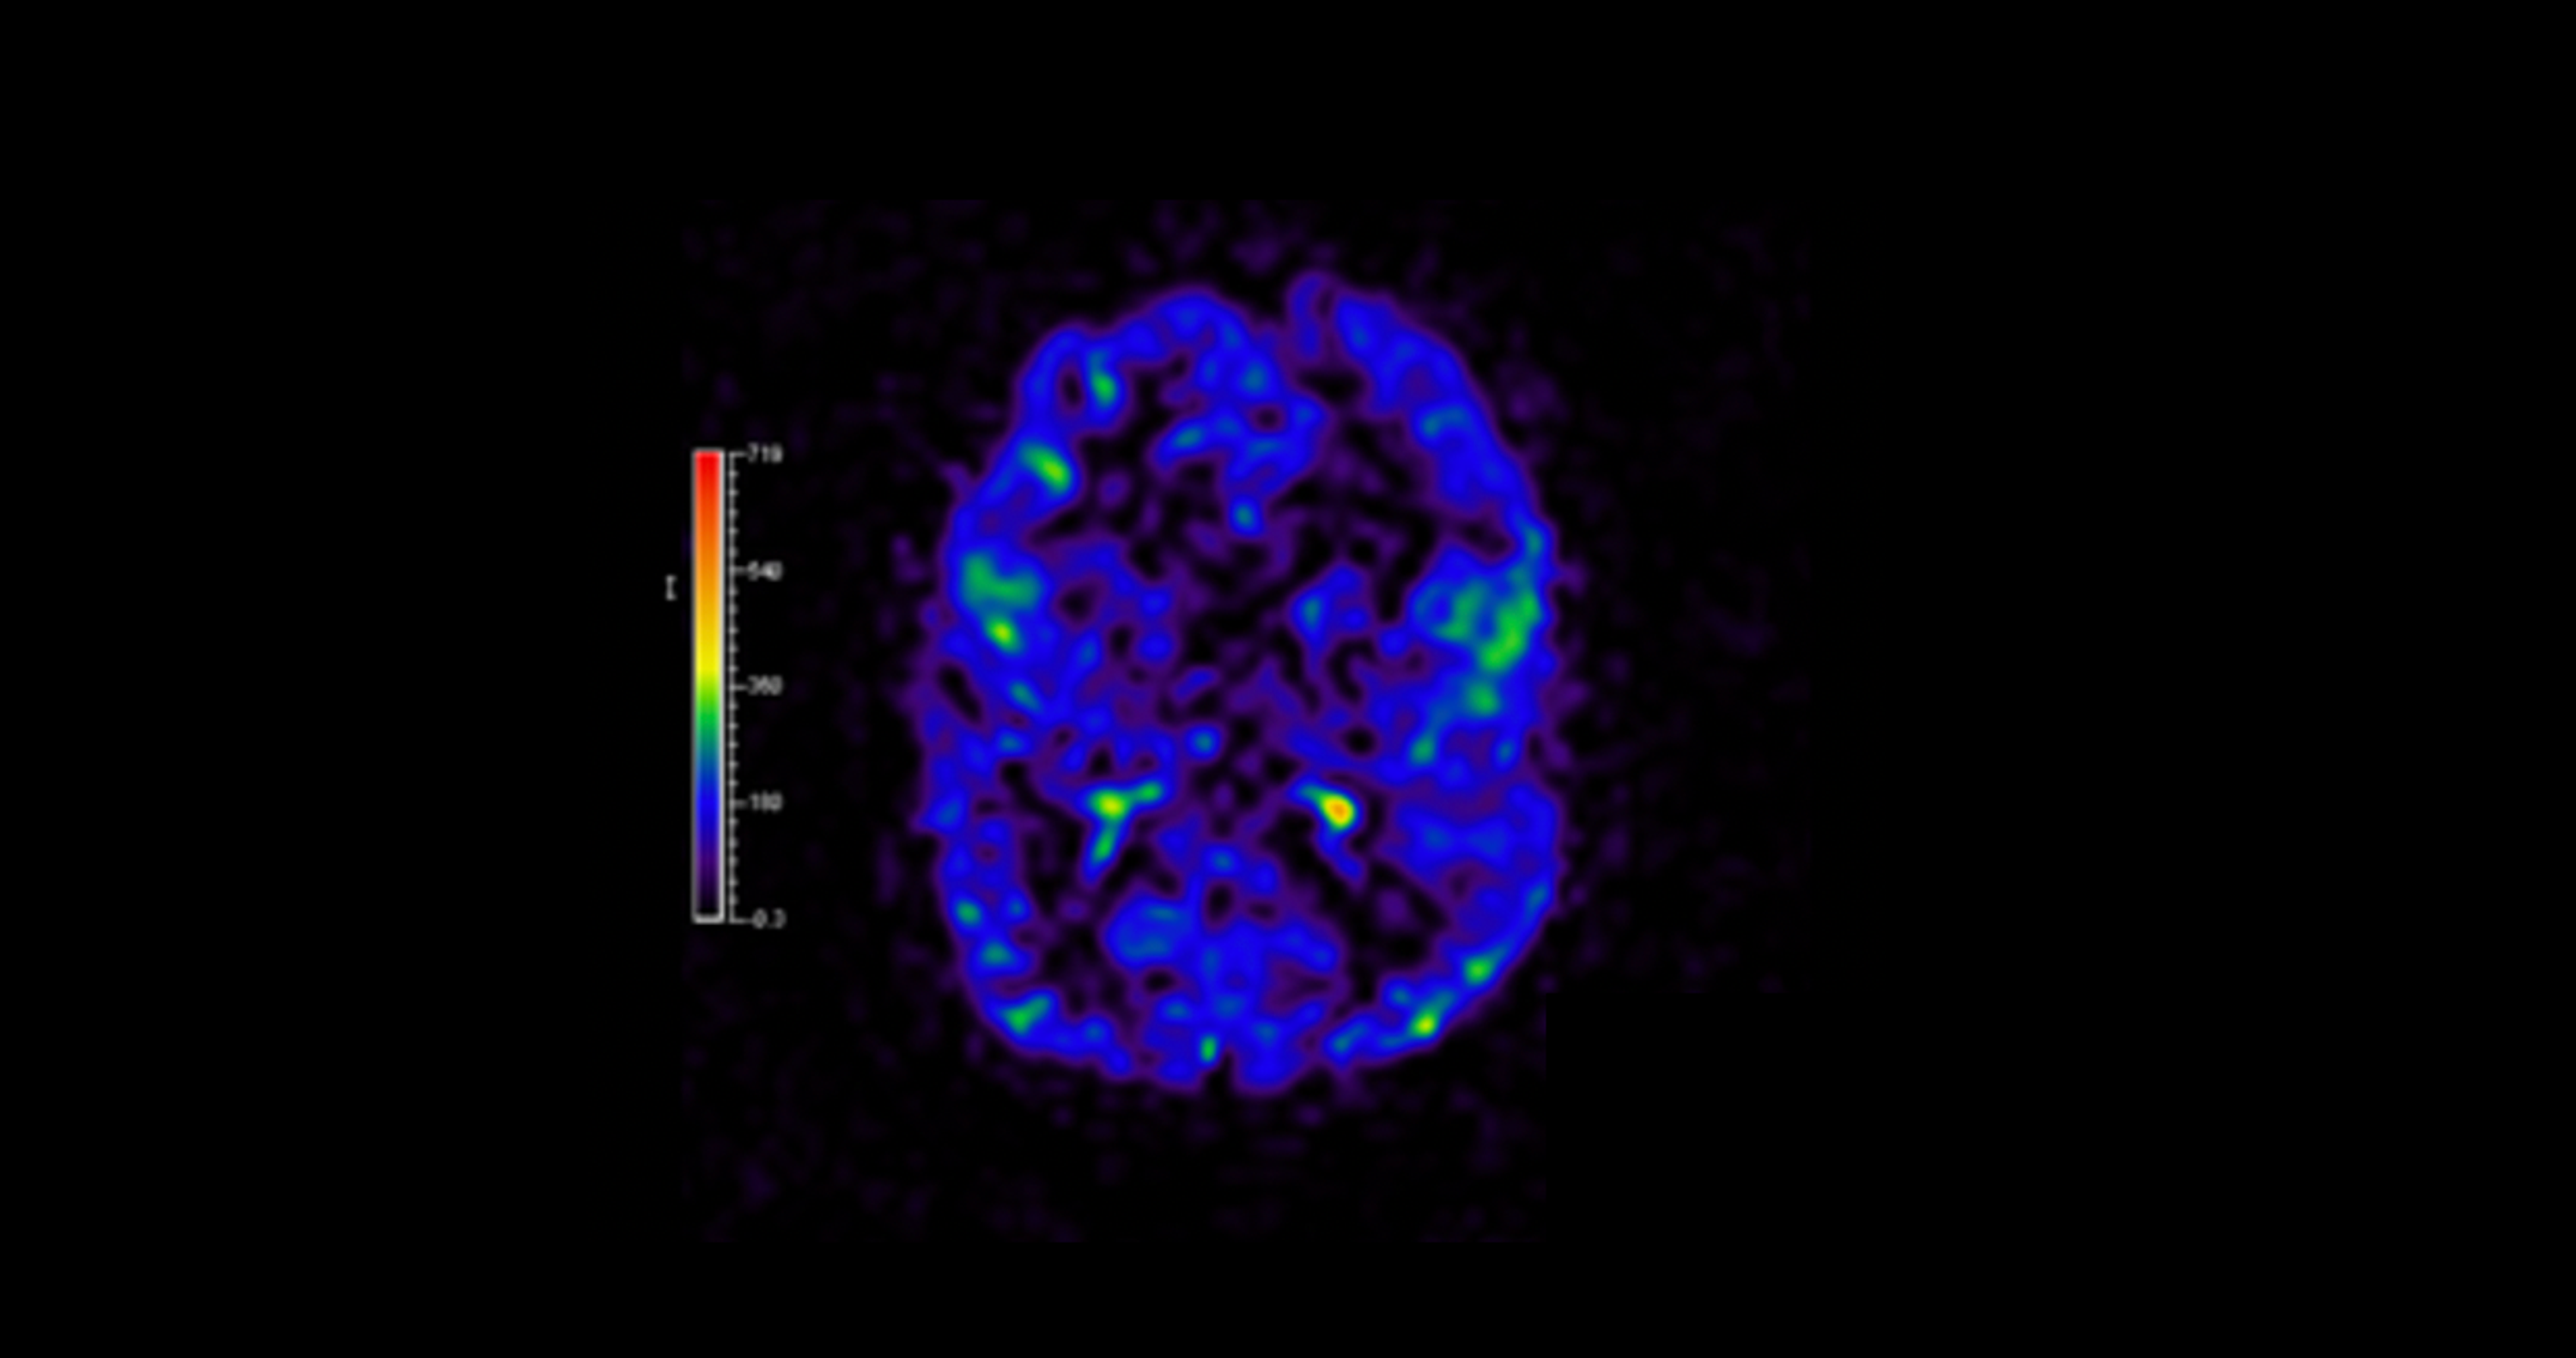

Megalencephaly Syndromes Exome Pipeline Strategies For Detecting Low Level Mosaic Mutations Plos One